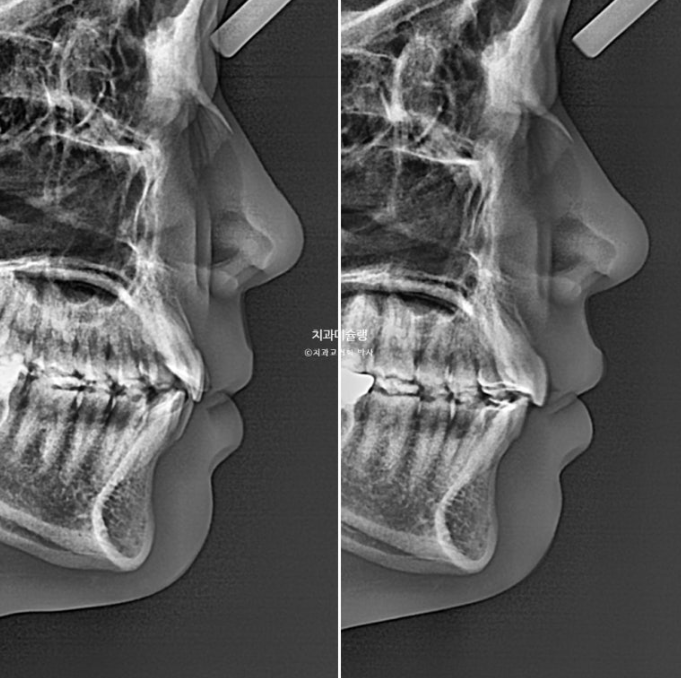

이제 안모 비교 보겠습니다.

예쁜 입매는 잘 유지되었습니다.

치료결과를 보면 이렇습니다.

앞니 위치와 각도, 입술 위치 모두 초진과 그대로 유지되었습니다.